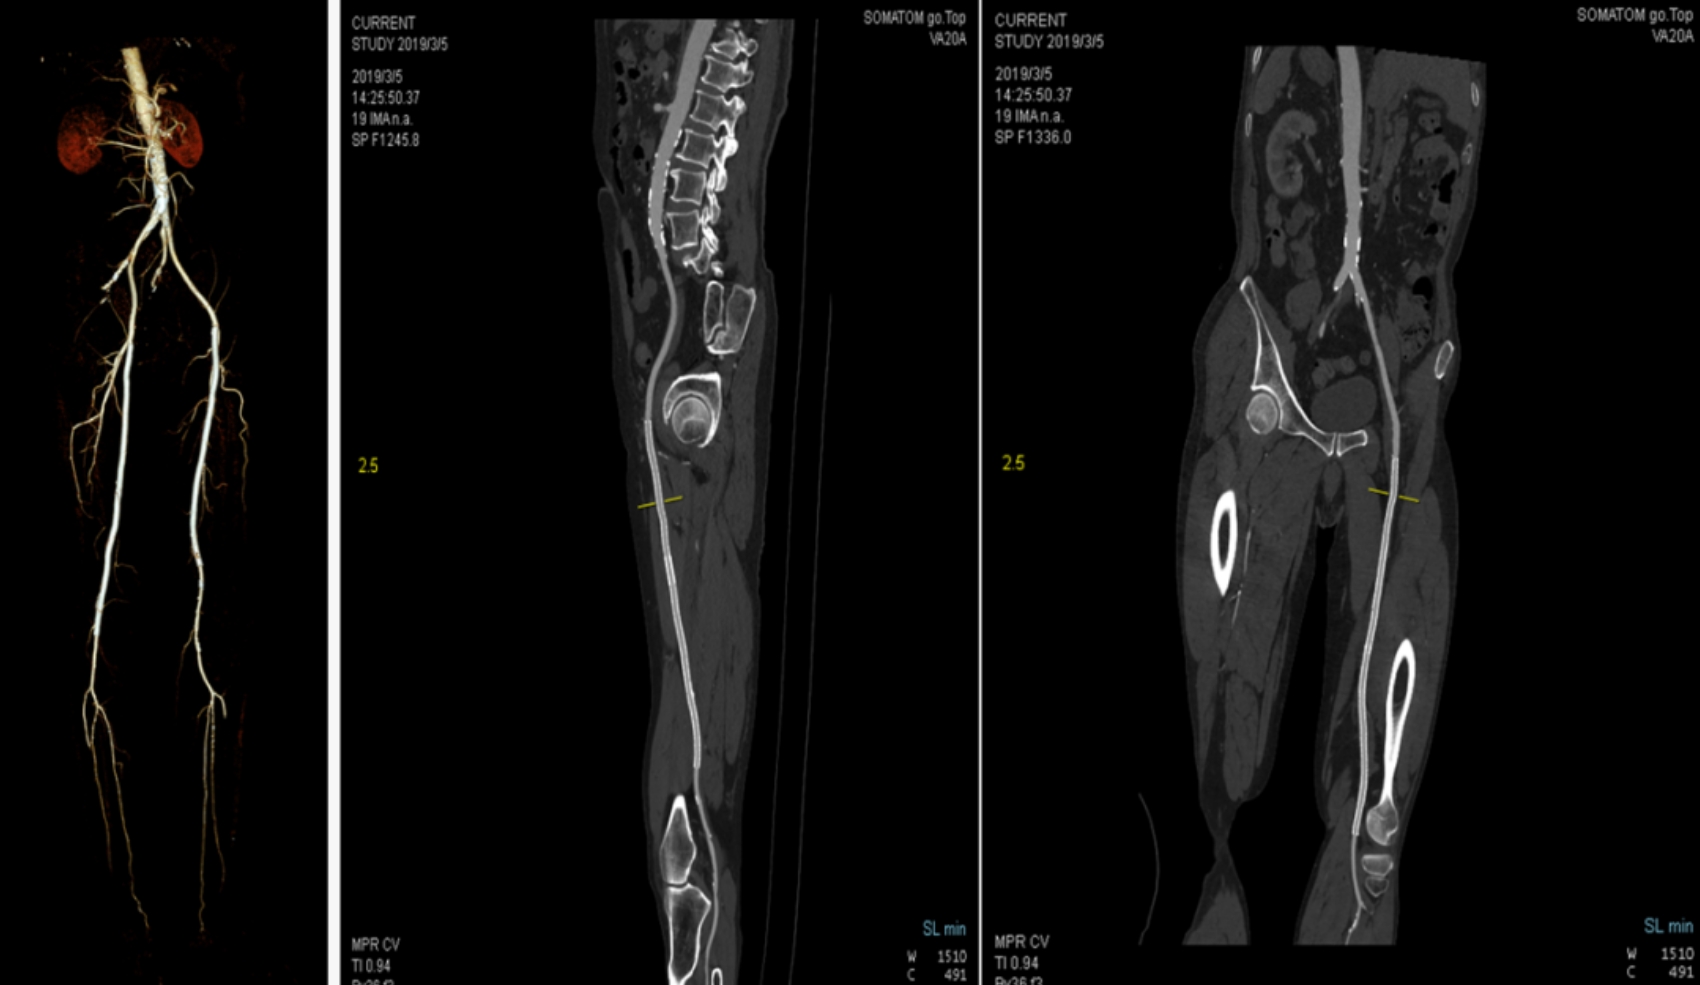

本次引進(jìn)的全新64排128層人工智能螺旋CT具有檢查更加精細(xì)、圖像更加清晰、掃描速度快和輻射劑量小等多種優(yōu)點(diǎn)。除了可進(jìn)行常規(guī)CT檢查、普通增強(qiáng)CT檢查外,還可對(duì)全身大血管、腦血管、心臟血管進(jìn)行檢查;強(qiáng)大的三維重建功能可發(fā)現(xiàn)普通DR、常規(guī)CT所難確診的病變。

該設(shè)備,可以在短時(shí)間完成對(duì)冠狀動(dòng)脈缺血、肺栓塞、主動(dòng)脈瘤的一站式檢查,也可在在短時(shí)間完成對(duì)頭部血管、頸部血管、腦實(shí)質(zhì)血液灌注的一站式檢查,為腦卒中和急性胸痛患者的早期診斷和治療能力贏得黃金時(shí)間。